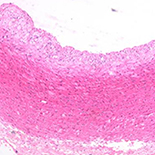

After 8 weeks of a high-fat diet, rabbit carotid arteries showed early atherosclerotic lesions. With increasing time after surgery, carotid artery and jugular vein grafts showed histopathological and morphological changes, including smooth muscle cell migration, lipid deposition, intimal hyperplasia, and vascular stenosis. The degree of vascular stenosis was significantly higher in vein grafts than in artery grafts at all time points – 35.1±6.7% vs. 16.1±2.6% at Week 12, 56.2±8.5% vs. 23.4±3.4% at Week 16, and 71.2±1.3% vs. 25.2±5.3% at Week 20.